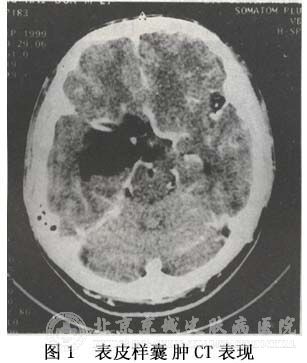

北京京城皮肤医院的皮肤专家王教授介绍说,表皮囊肿在临床上有多发也有单发。它是由于胚胎在发育过程中神经滞留引起的一类疾病。在临床上要鉴别诊断表皮囊肿也有通过组织病理来进行。

通过组织病理我们发现了表皮囊肿的形状是圆形的,也有椭圆形。经过检查我们发现囊璧里有大的血管进行相连,这些囊璧属于半透明的,与周围的脑组织界限比较清晰。这些囊璧进入了其他组织的各个角落甚至是脑池内,不仅给手术治疗增加了难度还给患者带了复发的可能性。这些表皮囊肿的包膜比较完整,可以检查出是否出现钙化,因为一旦出现钙化,就要延缓动手术的时间。